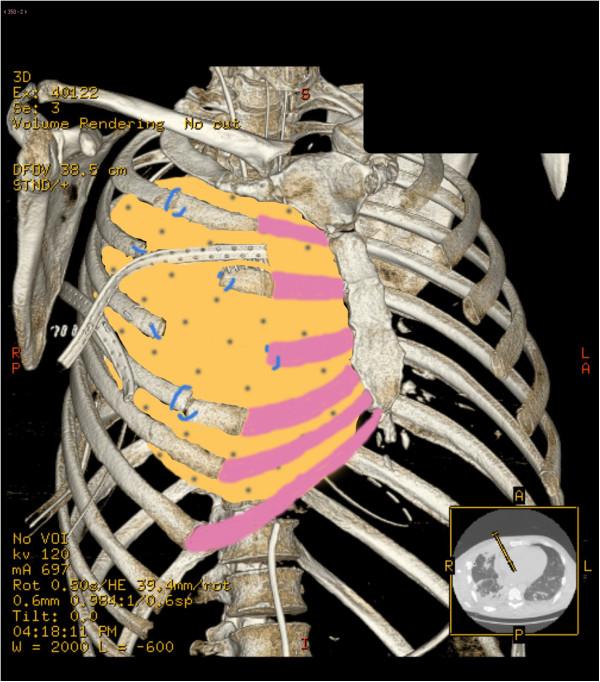

Despite progress in reconstructive techniques, rebuilding portions of the thorax remains challenging, in particular when large resections, contamination or infection are involved. No other cases of thoracic reconstruction in trauma patients with biological prosthesis have been described since now.

We report a case of thoracic reconstruction in highly infected field in a trauma patient. We also performed a literature review about the topic.

Collamend® demonstrated its usefulness in thoracic wall reconstruction even in trauma patients and infected fields.

尽管在重建技术方面取得了进展,但重建胸部部分仍然具有挑战性,特别是在涉及大切除、污染或感染的情况下。自那时以来,尚未有其他关于创伤患者使用生物假体进行胸部重建的病例报道。

我们报告了 1 例创伤患者在高度感染的情况下进行的胸部重建。我们还对该主题进行了文献回顾。

Collamend®在胸壁重建中表现出了其有效性,即使是在创伤患者和感染部位。